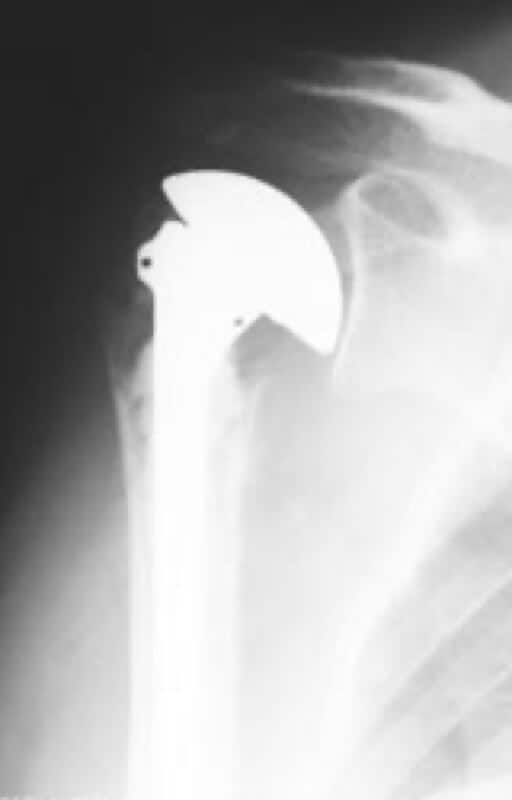

DePuy, Global Fracture